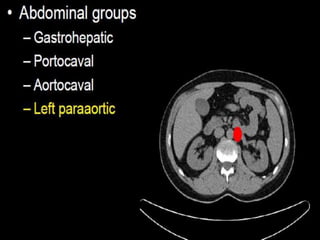

CT cross sectional anatomy.